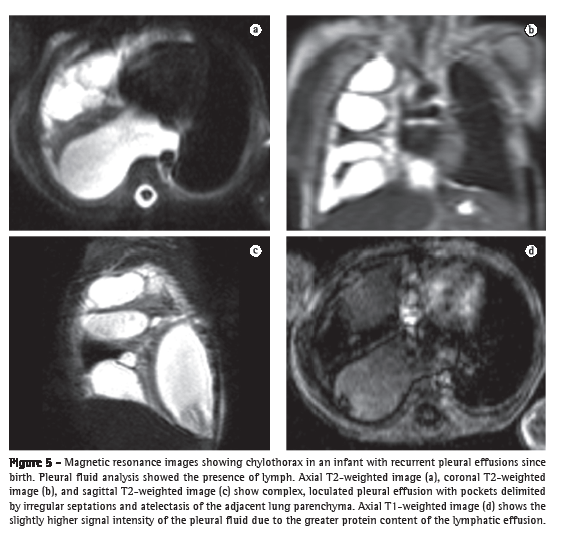

In the detection and characterization of pleural effusions, which commonly appear with high T2 signal intensity and low T1 signal intensity, varying according to the water and protein content, MRI is superior to X-rays and ultrasound. In comparison with CT, MRI is also superior, principally in the characterization of complex effusions (more clearly showing the septations in loculated effusions) and in the identification of exudates and hemorrhages (which show high T1 signal intensity), as well as of old bleedings, with peripheral areas of hypointensity due to hemosiderin deposition (Figure 5).(38)